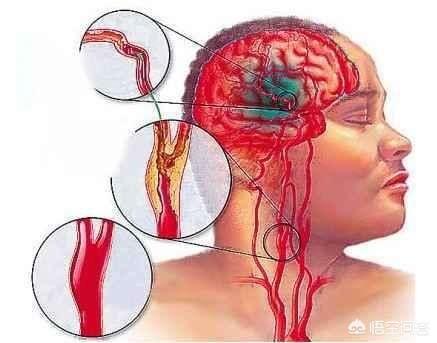

Notre cerveau gère presque toutes les fonctions de notre corps et est connu comme le commandant du corps. Le cerveau dépend du sang pour transporter l'oxygène et les nutriments dont il a besoin. Lorsque les vaisseaux sanguins sont bloqués pour diverses raisons, le cerveau est incapable d'obtenir de l'oxygène et des nutriments et meurt, entraînant la perte de fonctions de notre corps, ce qui est appelé infarctus cérébral. Les fonctions des différentes parties du cerveau étant différentes, les patients auront des séquelles plus ou moins importantes selon la localisation et l'étendue de la nécrose. Certaines personnes peuvent n'avoir qu'un léger vertige et découvrir qu'elles ont subi un infarctus cérébral lorsqu'elles se rendent à l'hôpital pour un examen (la plupart des patients atteints d'infarctus cérébral lacunaire sont découverts au cours de l'examen). Certains patients garderont des séquelles telles que l'hémiplégie, l'immobilité, la cécité, le retard mental, voire la mort.

L'infarctus cérébral est en fait un trouble de l'irrigation sanguine des vaisseaux sanguins du cerveau, qui se traduit par une irrigation sanguine insuffisante du cerveau, ce qui déclenche l'ischémie et l'hypoxie et aggrave encore la nécrose ischémique ou le ramollissement du tissu cérébral. L'infarctus cérébral représente la majorité des accidents vasculaires cérébraux dans la pratique clinique, et les types d'accidents vasculaires cérébraux les plus courants sont les suivantsThrombose cérébrale, infarctus lacunaire et embolie cérébraleetc.

L'infarctus cérébral est divisé en plusieurs types en fonction des différentes causes de l'infarctus : la rupture de la plaque causée par l'athérosclérose, formant un thrombus qui bloque les vaisseaux sanguins cérébraux, forme un infarctus cérébral ; l'embolie formée dans la région du cœur en raison d'une fibrillation auriculaire, d'un flutter auriculaire, d'une insuffisance cardiaque, d'une maladie valvulaire cardiaque, etc., qui pénètre dans les vaisseaux sanguins cérébraux avec le flux sanguin pour bloquer les vaisseaux sanguins cérébraux, forme également un infarctus cérébral ; l'occlusion des petits vaisseaux sanguins des artères cérébrales en raison d'un durcissement et de lésions, etc. forme également un infarctus cérébral, et ces infarctus cérébraux se produisent lentement en termes de pathogenèse. Ces infarctus cérébraux, bien qu'ils soient lents à se produire, mais lorsque les vaisseaux sanguins cérébraux sont soudainement bloqués, en particulier les vaisseaux sanguins importants responsables de l'approvisionnement en sang du cerveau, l'infarctus cérébral se produit d'un seul coup et il n'y a pas trop de précurseurs pour que nous puissions y faire face. L'infarctus cérébral se produit directement lorsqu'il entraîne directement dans le corps une hémiplégie, une aphasie, une ataxie, qui peuvent être accompagnées de maux de tête sévères, de nausées, de vomissements et d'autres symptômes, et l'état peut rapidement évoluer vers un infarctus cérébral. Par conséquent, pour prévenir l'infarctus cérébral, nous devrions toujours contrôler activement le risque à partir de la pathogenèse, et l'idée de se fier aux précurseurs ou aux symptômes précoces pour juger du risque d'infarctus cérébral est très difficile à mettre en œuvre pour prévenir le risque et intervenir à l'avance.

L'infarctus cérébral est également appeléInfarctus cérébral ou accident vasculaire cérébral ischémique (AVC ischémique cérébral)Ce terme désigne la nécrose ou le ramollissement du tissu cérébral dû à un manque d'apport sanguin au cerveau, qui se produit à la suite d'une ischémie ou d'une hypoxie.